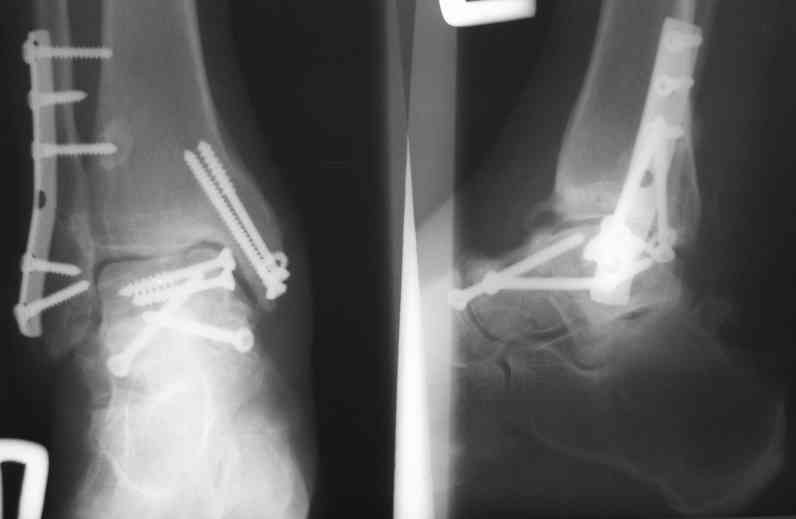

В Вашей ситуации мы произвели открытую репозицию и фиксацию металлоконструкциями. Все зажило первично, посттравматического дефартроза избежать не удалось. Пациент от артродезирующих операций в отдаленном периоде отказался.

Пациент отказался от артродезирующих операций потому что его устривает качество жизни или были какие-то другие причины (в итоге таран выглядит жутковато)